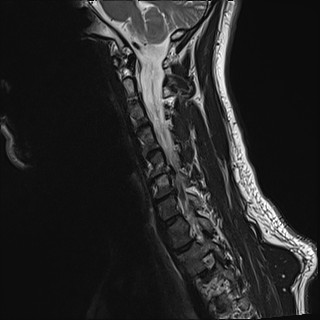

Wirbelsäule HWS

t2_tse_sag